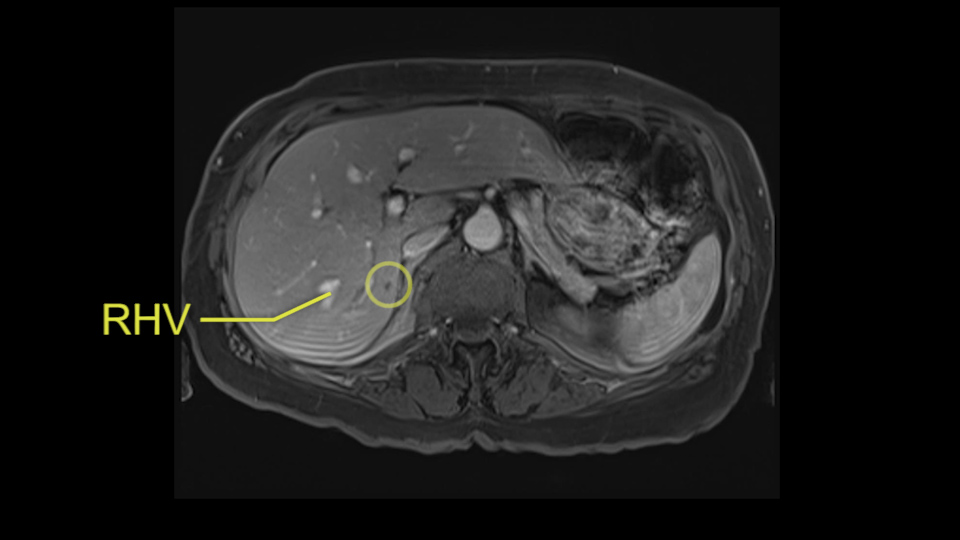

The procedure-specific slowing down moments from a technical point of view for a right hemihepatectomy include a careful evaluation of the inflow structures including the right hepatic artery, the right portal vein, as well to make sure that I have identified and preserved the left hepatic artery and the left portal vein at all times, and minimize any injury or dissection of the common bile duct. Also, I am careful when I mobilize the right liver, not to tear the right triangular ligament and cause bleeding of the liver as I mobilize it off the retroperitoneum and the bare area. In addition, the last procedure-specific slowing down moment is to carefully identify the right hepatic vein and ensure that I encircle it safely without damaging the IVC or the middle and left hepatic vein structures at all times.

So I would then focus on the hepatic outflow because that’s the way we do the operation is by mobilizing the liver. So the vena cava looks quite normal. The right hepatic vein looks quite normal. There are no large additional outflow veins from the right lobe which would generate slowing down moments. The hepatic artery is unremarkable and is not usually an issue we can define the anatomy quite clearly at surgery.

Coming up a little bit higher. There’s a little bit of biliary dilatation as well. On the right side of the liver. Which may be nothing but it may be an indicator or harbinger of nodal disease in the hepatoduodenal ligament so something to be aware of. If the enzymatic liver function tests are normal and there’s no evidence of a stone in the common bile duct on cross sectional imaging you wouldn’t need to do anything about it but just to be aware of that.![[RHV]](jpg/preop_as_p4.jpg)

So we’re going through the liver segments now. Here we’ve got the inflow; here’s the main portal vein, right anterior sectoral portal vein, right posterior sectoral portal vein there. Here’s the main here going to the left lobe first of all. So that’s 3 and 2 there, they look clear, and there’s a good size of the left lobe with a good girth. So 3 and 2 look clear. There are usually more feedback branches from the left portal vein to segment 4b but that also looks relatively clear. There’s a little more disease over on the right side there. So that would be...right hepatic vein here...that’s Segment 7. So we’ve got disease in 7, 5, probably in 6 on the right side; at least 3 lesions. That’s the distribution of the lesions.![[Ant. RPV] [Main PV] [Post. RPV]](jpg/preop_as_p5.jpg)